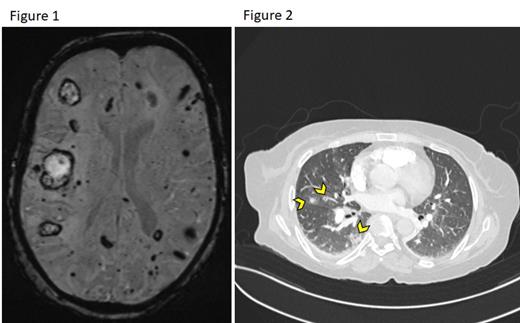

She received first-line therapy with a 5-day course of Cladribine (0.15 mg/kg/day) with initial resolution of leukocytosis, normalization of platelets, and a 50% reduction in spleen size. This was followed by consolidation with an 8-weekly course of Rituximab (375 mg/m 2). Soon after the 2 nd dose of Rituximab, leukocytosis recurred, and she was initiated on second-line therapy with Bendamustine (90 mg/m 2 on days 1 and 2) along with Rituximab (BR). She has not achieved any durable response following two cycles of BR. Unfortunately, she suffered a septic shock requiring admission to our intensive care unit. Upon routine mental status evaluation, brain MRI revealed innumerable supratentorial and infratentorial bilateral acute/subacute and old microhemorrhages (Figure 1). This prompted further evaluation of unexplained recurrent episodes of pulmonary hemorrhages while on mechanical ventilation that were found to be secondary to pulmonary end-arterial cavitating lesions suggestive of hairy cells infiltration (Figure 2 arrowheads). As she was clinically unstable, we attempted to control leukocytosis with corticosteroids, leukapheresis aggressively and started the patient on Ibrutinib, but she succumbed to her disease.

Recently, the 5 th edition of the World Health Organization classification of hematolymphoid tumors highlighted the splenic B-cell lymphoma and leukemia family that encompasses hairy cell leukemia (HCL), splenic B-cell lymphoma/leukemia with prominent nucleoli (SBLPN), formerly known as hairy-cell leukemia variant, splenic diffuse red pulp small B-cell lymphoma (SDRPL) and splenic marginal zone lymphoma (SMZL). HCL is typically an indolent mature B-cell neoplasm with characteristic pathologic features that preferentially insinuate the bone marrow and the spleen causing impaired hematopoiesis and splenomegaly. Unlike other disorders within this group, HCL commonly harbors BRAF V600E somatic mutation in almost all cases. Rarely, patients with HCL can have extramedullary involvement by the malignant cells. Leukocytosis in HCL appears to increase the risk of developing extramedullary lesions that can present unique clinical challenges necessitating early and effective therapy. According to the literature, brain lesions in HCL were described in three other cases, and leukocytosis was a common denominator. Our patient with significant leukocytosis had brainand pulmonary lesions, and the latter was the cause of her demise due tounusually aggressive and refractory disease. Therefore, we hypothesize that leukocytosis in HCL can be “the tip of the iceberg”. The higher the leukocytosis, the higher the burden of extramedullary disease, as in our case, who had simultaneous lesions in the brain and lungs. Patients with HCL and leukocytosis may warrant initial diagnostic evaluation to ensure the absence of potentially sinister lesions, which can inform subsequent monitoring and management plans. Additionally, more novel therapies could be considered sooner in the treatment course to control the disease and these lesions. Finally, our patient did not harbor BRAF V600E mutation, which likely resulted in further worse outcomes and limited the usage of targeted therapies like BRAF inhibitors.